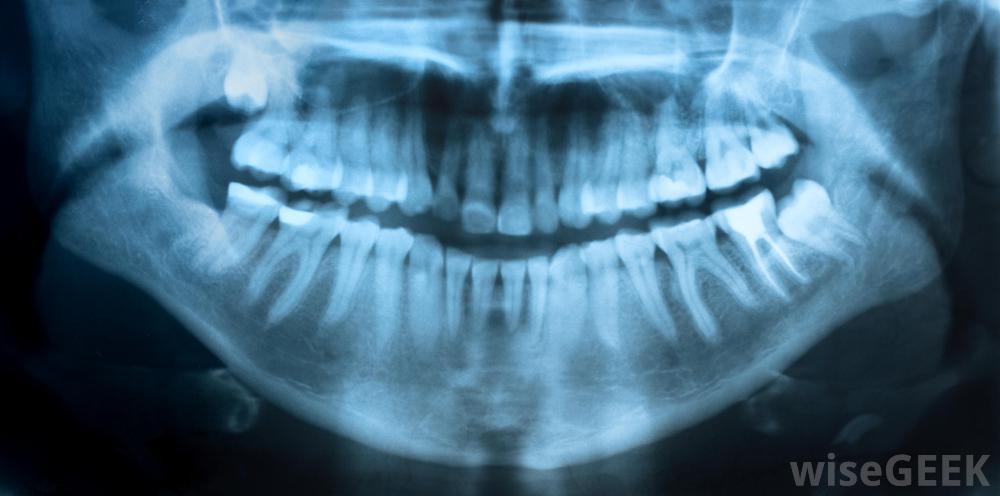

X光片是磨牙根管的组成部分。

磨牙根管可能需要几个小时。对感染的牙齿进行X光检查,以确定有多少根根管存在,以及在哪里进行治疗。磨牙可以有两到四根根根管,可能需要多次就诊有些情况下,在磨牙根管手术之前、期间或之后,可能会使用抗生素。